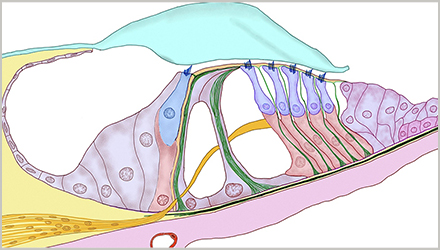

正常情况下,内耳毛细胞负责将外耳收集、中耳传导的声音转化为电脉冲,然后由听觉神经传送至大脑,再由大脑解读为可识别的声音。

感音神经性听力损失意味着,内耳毛细胞或连接内耳与大脑的神经通路受损。感音神经性听力损失是永久性的听力损失,目前我们无法通过手术来修复已受损的毛细胞,国际上通常建议使用助听器进行助听补偿。

耳蜗硬化症:硬化侵入耳蜗,并对连接内耳与大脑的感觉毛细胞或神经通路造成永久性损伤,从而引起感音神经性听力损失,这种情况下镫骨切除术也无效果。